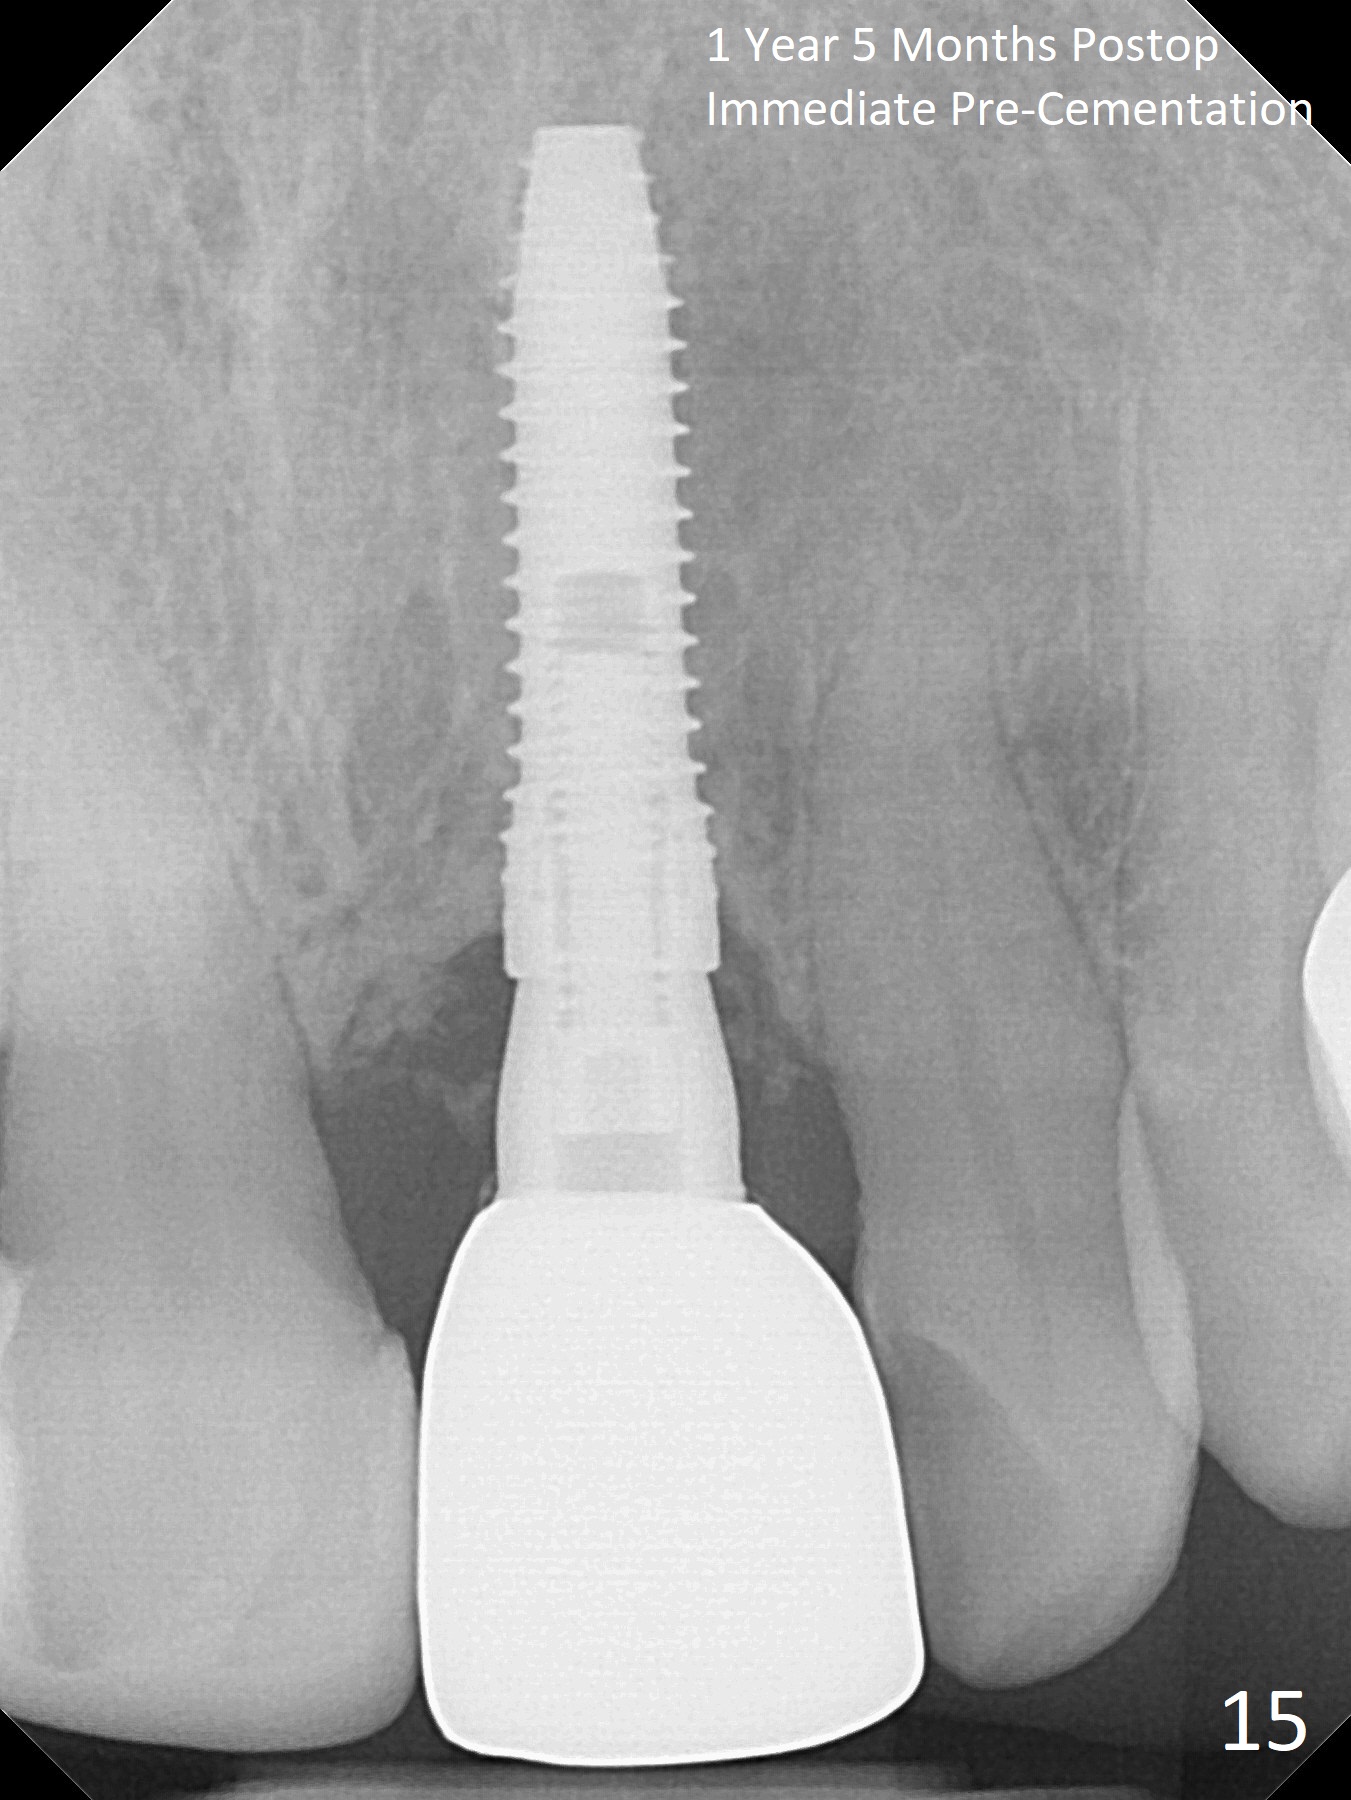

In spite of the incisobuccal shift of the tooth #9 with gingival recession (Fig.1) and loss of the buccal plate (intraop finding), there is no buccal contour collapse (Fig.2 *), due to the presence of the buccal bone of the neighboring teeth and the root of the affected tooth. After extraction, osteotomy (Fig.3) and dummy implant try in (Fig.4), a definitive implant is placed palatally with the buccal gap (Fig.5 *). In fact there is mild buccal contour collapse prior to bone graft (Fig.5 arrow). When allograft (Vera, Fig.6,7 *) is packed buccal to the implant and overlying abutment as a solid support, the buccal contour seemingly returns normal (Fig.6 arrowhead). An immediate provisional is fabricated to prevent loss of the bone graft during healing period. Bone graft kept in place by the provisional turns yellow 6 days postop (Fig.8). The buccal plate remains strong, while the fistula becomes indistinguishable. After adjustment of the provisional margin a few times (nearly 3 months postop, Fig.9,10), the gingival margin appears to have grown incisally, as compared to Fig.1. There is minimal buccal bone collapse (Fig.10). Dislodgement of the abutment and provisional forces her to return 1 year 4 months postop; the socket has healed (Fig.11). The buccal plate is not concave 1 year 4 months postop (Fig.12). The gingiva is slightly recessive (Fig.13) with mild buccal plate concavity (Fig.14) immediately before cementation. The implant could be placed ~ 1 mm deeper (Fig.15).